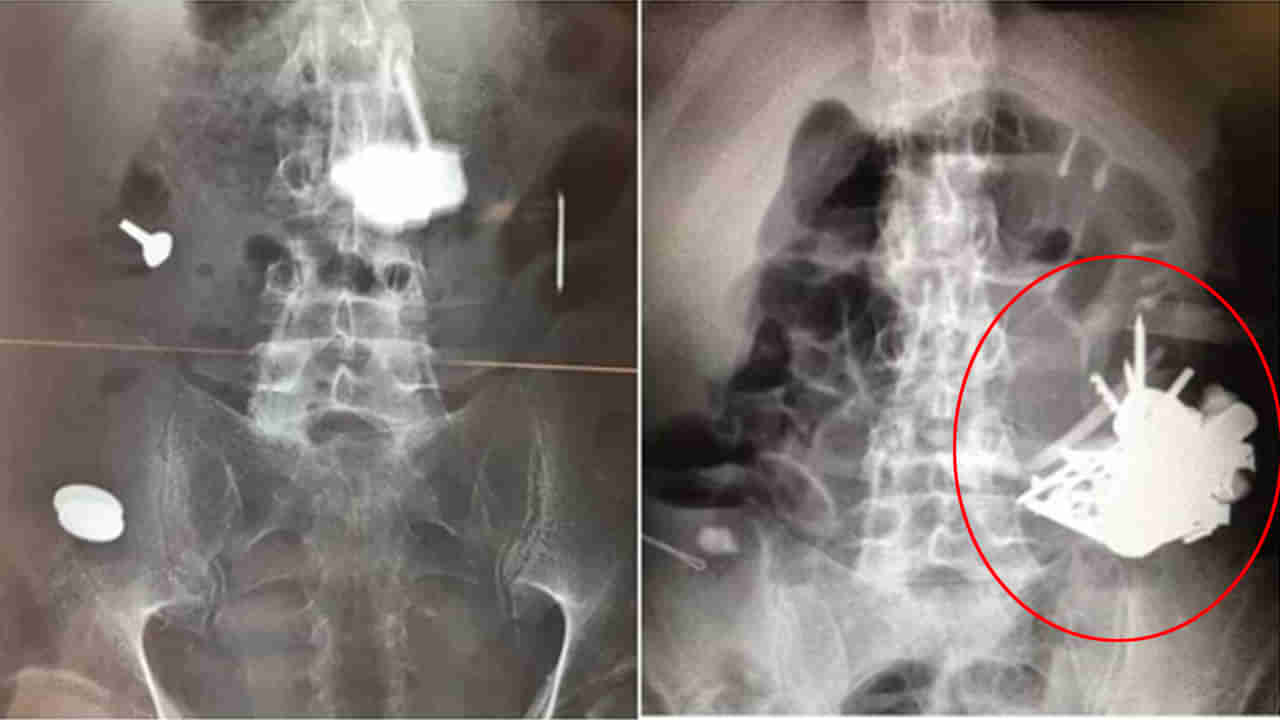

బీఎంజే జర్నల్స్లో ప్రచురితమైన ఓ నివేదిక ప్రకారం.. ఫ్రాన్స్లోని డాక్టర్లు 52 ఏళ్ల వ్యక్తి కడుపులో నుంచి ఏకంగా 100 లోహపు వస్తువులను తొలగించారు. సైకోసిస్ అనే అరుదైన వ్యాధితో బాధపడుతున్న సదరు వ్యక్తి.. ఉద్దేశపూర్వకంగా లోహపు వస్తువులు తినే అలవాటు ఉందట. కత్తులు, స్క్రూలు, గింజలు, చెంచా హ్యాండిల్స్, స్క్రూడ్రైవర్ హెడ్, వాషర్, గులకరాళ్లు, నాణేలు, ఇనుప తీగలు లాంటివి తినేవాడట.

ఆ వ్యక్తి ఐదు సంవత్సరాల కాలంలో ఐదుసార్లు ఆస్పత్రికి వచ్చాడట. కడుపు నొప్పి, వికారం, రక్తపు వాంతులు లాంటి లక్షణాలతో చేరాడు. ఇక అస్పత్రికొచ్చిన అతడికి పలు పరీక్షలు, టెస్టులు చేయగా.. ఎండియోస్కోపిలో పలు లోహపు వస్తువులు అతడి కడుపులో ఉన్నట్టు డాక్టర్లు గుర్తించారు. ఆ లోహ వస్తువులు అతని కడుపులో రంధ్రాలు చేసాయని.. అందువల్ల శస్త్రచికిత్స ద్వారా వాటిని బయటకు తీసహ్రు. ఆ వ్యక్తి మూడు నెలల కాలంలో ఈ లోహ వస్తువులను మింగాడని వైద్యులు భావిస్తున్నారు.